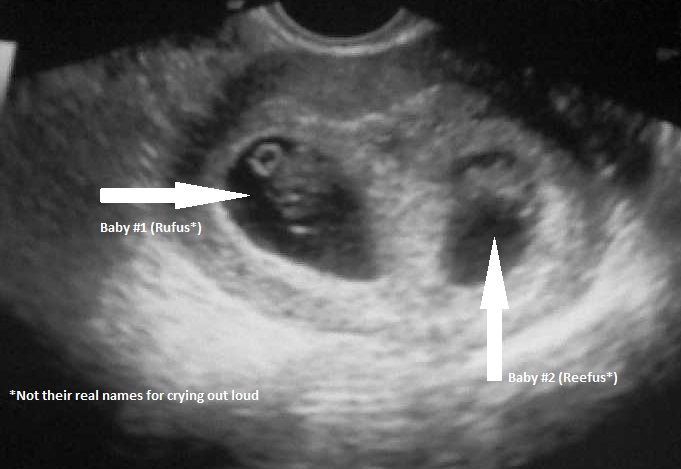

Meet babies-to-be Rufus and Reefus, who officially have heartbeats. We saw the hearts beating like two fluttering hummingbirds two days before my birthday. Happy birthday, indeed.

Though it was in the geneticist’s office for first trimester screening, we saw both babies active with Rufus face up and Reefus face down. It looked like they were dancing, and clearly, they thought no one was watching.